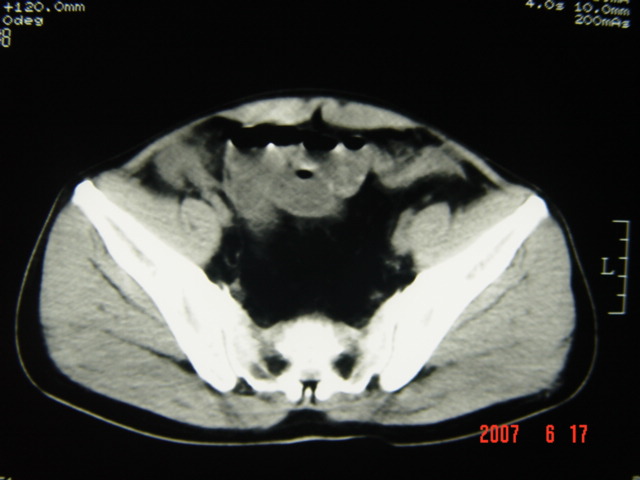

[br][br]以下是引用lkc8963在2007-6-17 13:32:00的发言:[br]完全支持邓主任意见:降/乙交界部占位性病变伴不全梗阻.做个增强或者be可能更好.